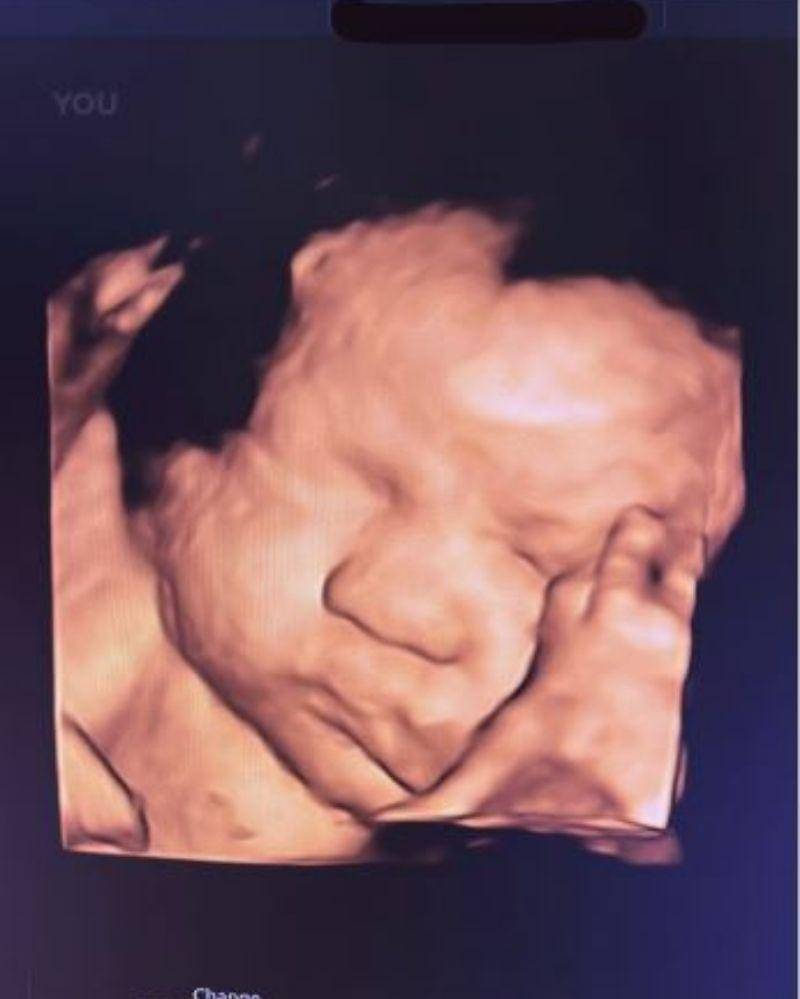

30. Ameena Hanna Nur Atta, anak Aurel Hermansyah dan Atta Halilintar

Kelahiran Ameena Hanna Nur Atta membawa kebahagiaan yang luar biasa bagi kedua orangtuanya, Atta Halilintar dan Aurel Hermansyah.

Bahkan, sejak masih di dalam kandungan sang Mama, kehadiran Baby Ameena sangat dinanti-nantikan, tak hanya oleh keluarga Atta dan Aurel, tetapi juga para penggemar keduanya.

Baby Ameena akhirnya lahir pada 22 Februari 2022. Ameena punya paras yang menggemaskan sejak masih di dalam kandungan ya, Ma!